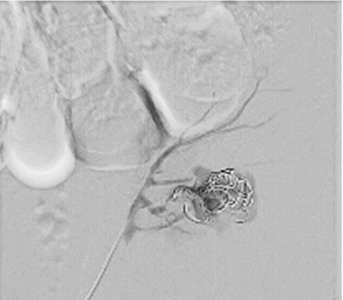

Right femoral artery was punctuated under local anesthetic. Inferior segmental artery was selectively catheterized and pseudoaneurysm was visualized. A microcatheter was inserted into segmental branch (Figure 4).

Pseudoaneurysm was embolized with two 8 mm x 20 cm coils, an additional coil of 12 mm x 30 cm (Figure 5).